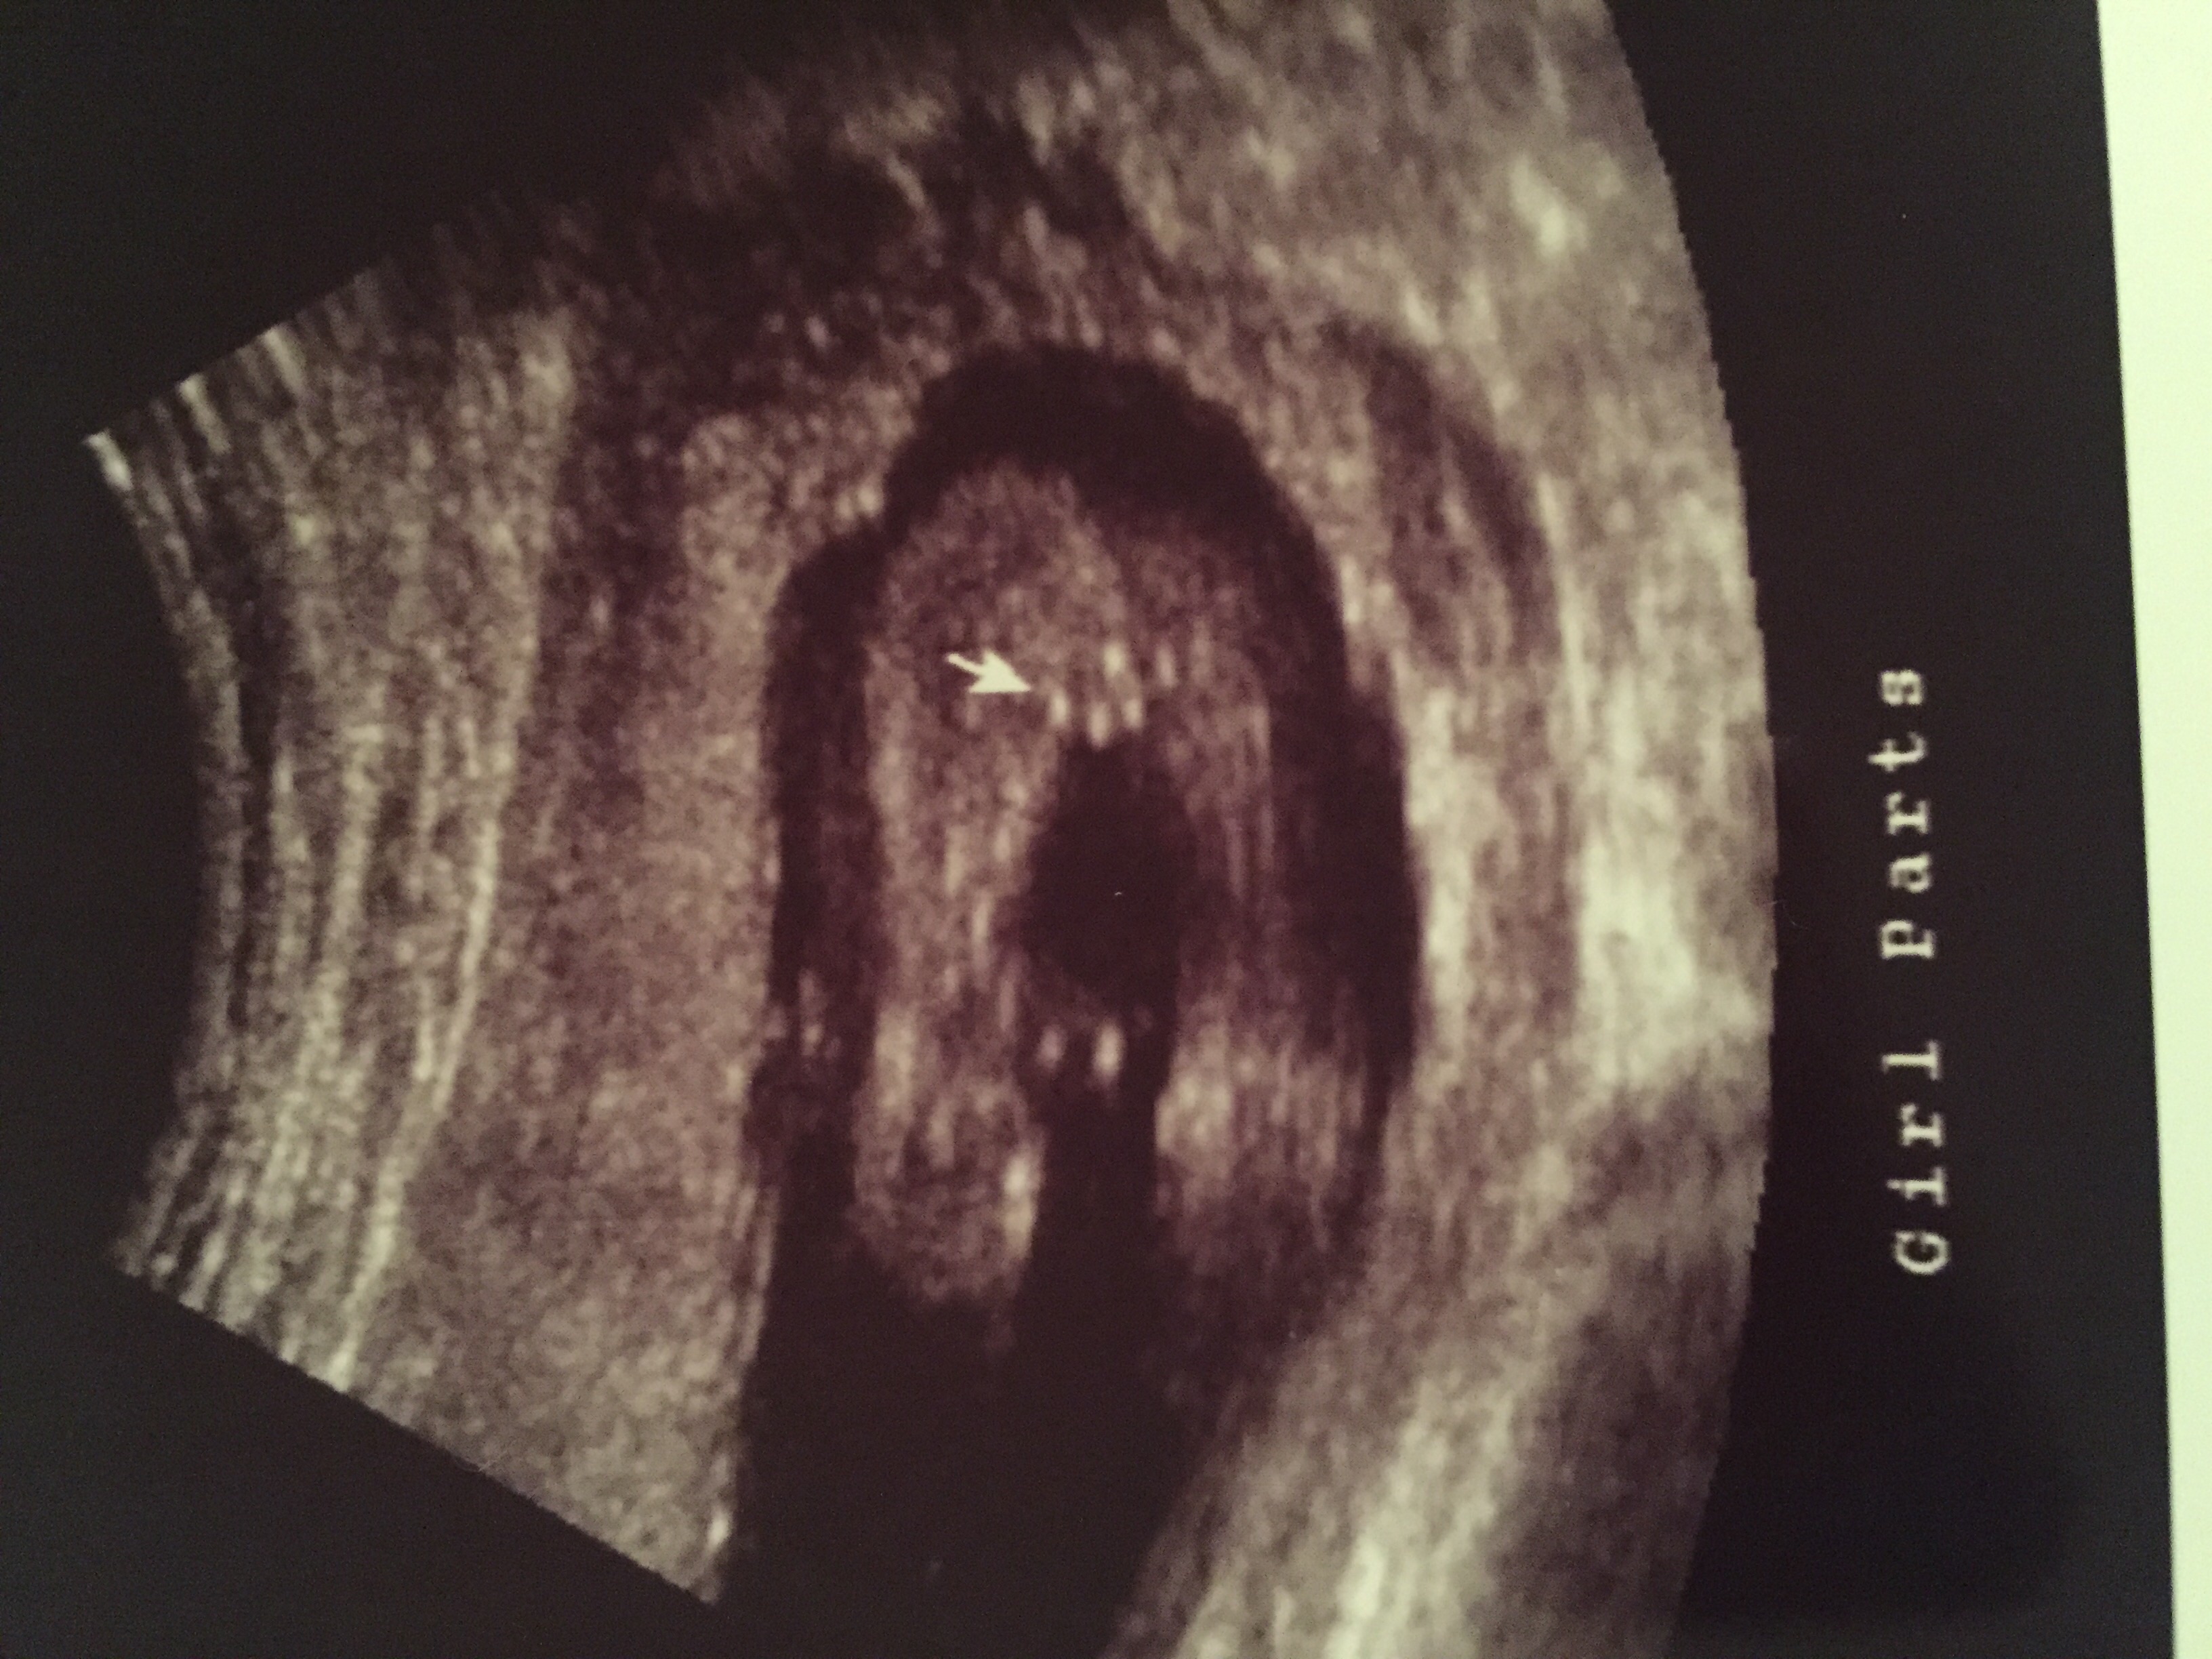

Just found out today 15 weeks! PINK! My 7 yr old daughter, Scarlett, was so excited she cried. We were thinking Penelope (penny)...but now hubby wants to look at ALL names again. Lol we will see